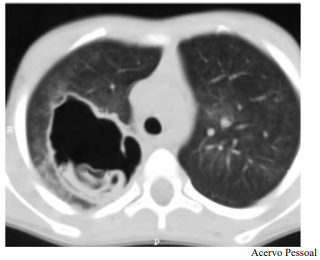

Determinado paciente de 49 anos de idade, morador em zona rural, iniciou com quadro de tosse importante, com piora progressiva, de início há dois meses, associada a alguns episódios de vômica. Refere febrículas na última semana. O paciente é tabagista leve, trabalha com criação de ovelhas e mora em casa com cachorros e gatos. Nega viagens internacionais recentes. Não foi encontrada nenhuma alteração no exame físico. Verificaram-se FC = 80 bpm, FR = 20 irpm e SatO2 = 99% em ar ambiente. A tomografia de tórax apresenta uma lesão cística de paredes espessas e conteúdo heterogêneo em seu interior, conforme representado na imagem a seguir.

Tendo em vista esse caso clínico e os conhecimentos médicos correlatos, julgue o item a seguir.

O órgão acometido pela doença infecciosa do paciente é o sítio preferencial de acometimento por esse germe, e o segundo órgão preferencial é o fígado.